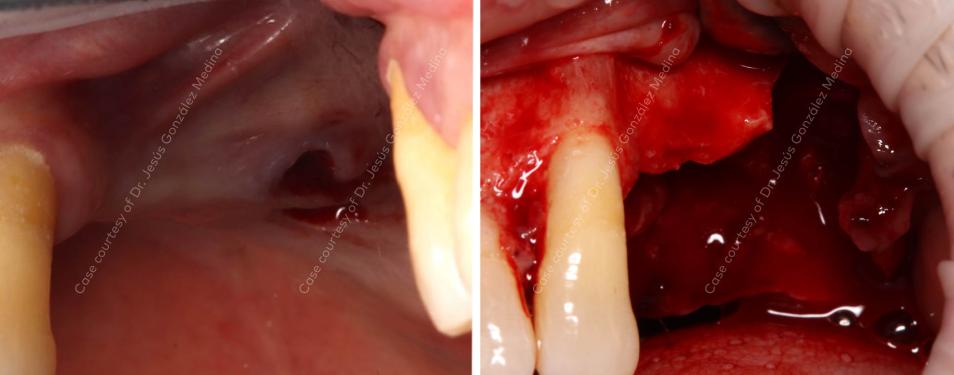

Patient: 67-year-old male with a complaint of difficulty with mastication and poor esthetics.

Clinical situation: Missing 24-25, and 26 exhibits grade III mobility, indicating severe bone loss vertically 11 mm at the deepest area and horizontally 2 mm, and chronic periodontitis.

Surgical solution: Extraction of 26 and vertical bone augmentation using creos syntoprotect Ti-reinforced PTFE membrane and 50% xenograft and 50% autologous bone to attain the necessary bone height for implant placement of NobelActive® TiUltra™ implants.